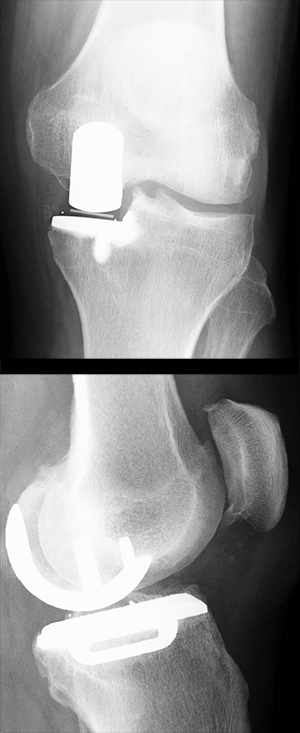

Wenn nur eine Seite des Kniegelenks verschlissen ist – meist ist es dann wie hier die innere – reicht es, nur eine Teilprothese einzusetzen. Der Eingriff ist weniger schwerwiegend als die Implantation einer Totalendoprothese.